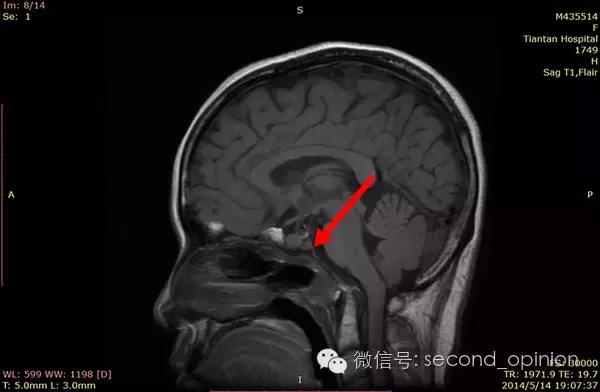

至2014年1月,出现左耳耳鸣,表现为低调杂音,未发现听力明显下降,偶有脸部麻木,无面瘫。行MRI检查,颅内占位范围约60*45*47mm。2014年2月2日第一次手术,行内镜导航下经蝶窦颅底肿瘤切除术,切除体积约50*45*50mm,手术顺利,术后头痛症状消失。左耳低调耳鸣术后消失两周后再次出现,右耳术后出现偶发轻度耳鸣。2014年5月4日第二次手术,行内镜口鼻蝶入路脊索瘤切除术,切除肿瘤体积45*40*50mm,过程顺利,术后耳鸣消失,病情稳定后出院。

2014年6月15日 进行射波刀放疗,32.5Gy/5fx,剂量曲线69%包绕,治疗期间对症脱水,减轻放疗反应,完成全部治疗后出院。

2014年12月 进行质子放射治疗。

日本国立癌症中心 2014年12月3日-12月31日

总剂量40GyE

2014年9月1日MRI(手术治疗前)

质子治疗前

2015年1月25日 对比质子治疗之前增强核磁共振影像无明显变化,脊索瘤放疗后变化缓慢,建议3月后继续复查。

2015年04月01日 对比增强核磁共振影像,同第一次复查。

2015年06月03日 对比增强核磁共振影像,对比第三次复查,肿瘤略有缩小。

质子治疗后第四次复查

目前患者生活质量良好,无复发转移。